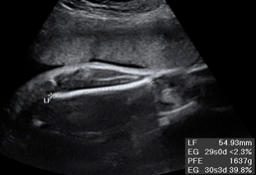

En la ecografía del tercer trimestre es muy difícil extraer una imagen completa del bebé. Rara vez se las apaña el ecografista para poder captar una "foto panorámica" de una criatura, que ya ocupa casi la totalidad del útero materno. Por eso, la mayoría de las ecos de esta edad gestacional se especializan en partes u órganos específicos del feto. El ecografista puede detectar aún ciertas anomalías del desarrollo, comprueba el líquido amniótico, el bienestar fetal y, muy importante, visualiza el cordón umbilical, que puede estar enrollado en algún órgano como cuello, pies o manos.